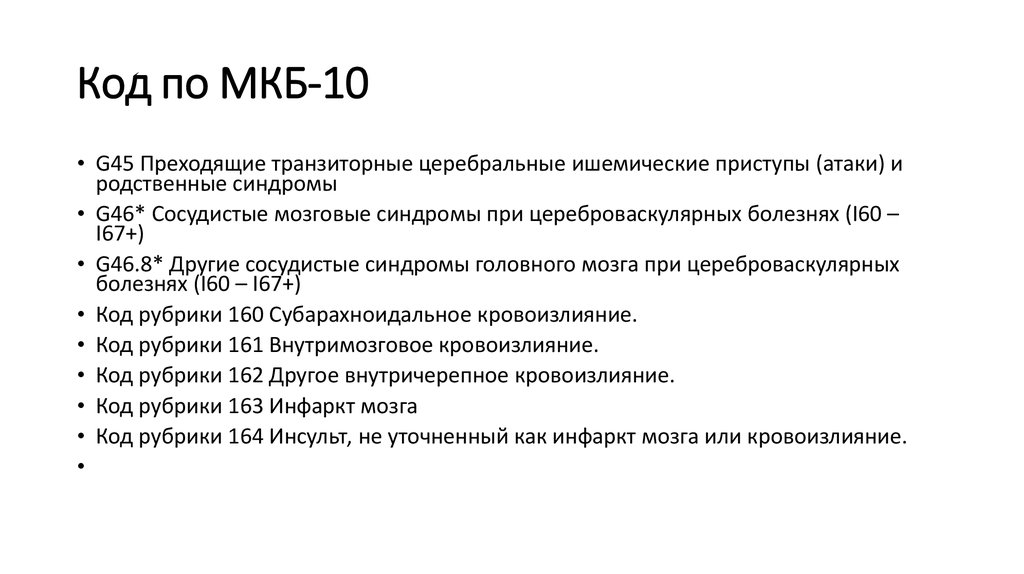

Код мкб 10 атерома головы

Код мкб 10 атерома головы 109 фото